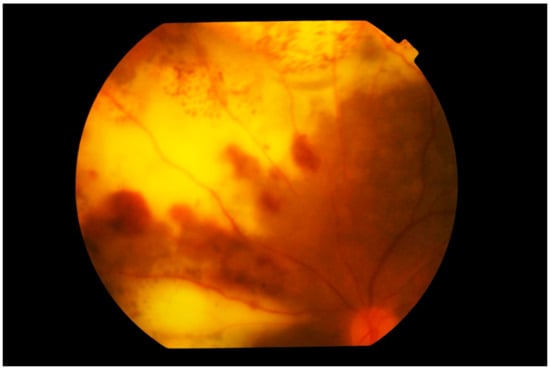

3. Clinical Features

Differential Diagnosis